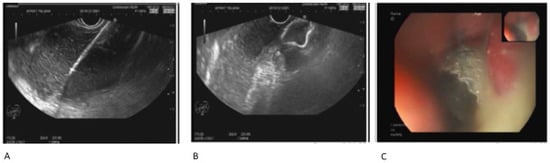

6. Necrotic Peripancreatic Collection Debridement

9. Endoscopic Step-Up Therapy

10. Timing of Direct Endoscopic Necrosectomy (DEN) of Walled-Off Necrosis (WON)